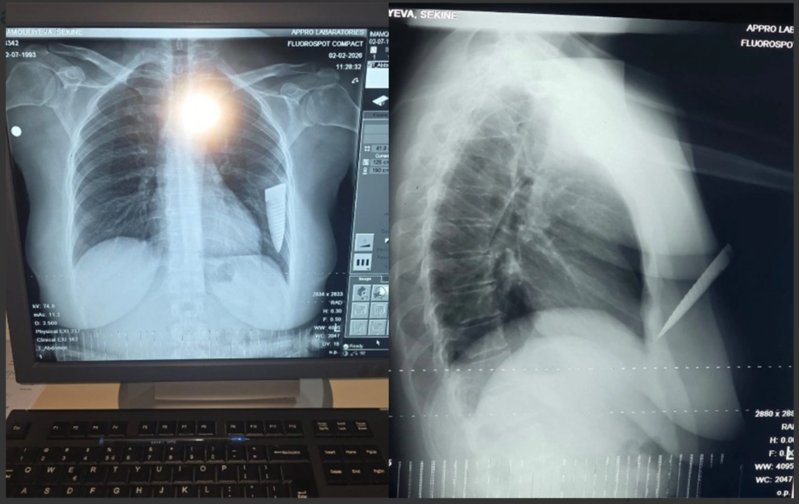

"Hadisə fevralın 1-də saat 19 radələrində yaşadığım Gəncə şəhərindən Şəmkirə dəvət edildiyim toy mərasimindən çıxarkən baş verdi. Şadlıq evinin qarşısında maşınıma minərkən əvvəllər qeyri-rəsmi münasibətdə yaşadığım Əli Kamran oğlu Əsgərov qəfil hücum etdi. O, gözlənilmədən maşınıma yaxınlaşdı, sağ ön qapını açaraq boğazımdan tutub boğmağa çalışdı. Daha sonra cibindən bıçaq çıxarıb dörd dəfə zərbə endirdi. Zərbələrdən biri ürək nahiyəmə, üçü isə sol qoluma dəydi. Həmin vaxt bıçaq qırılaraq döş qəfəsimdə qaldı, yoxsa daha çox zərbə endirib məni öldürə də bilərdi. Çünki bıçaqla ardıcıl olaraq məni vururdu. Bıçağın qırıldığını, ətrafdakı insanların səs-küyə gəldiyini görərək qaçıb getdi".

"Artıq münasibətimiz bitmişdi. Əli Əsgərov ayrılıqdan sonra məni mütəmadi izləyir, hədə-qorxu gəlirdi. Bıçaqlanandan sonra Şəmkir Rayon Mərkəzi Xəstəxanasına, oradan isə Gəncə Beynəlxalq Xəstəxanasına aparılaraq əməliyyat olundum. Döş qəfəsimdə qırılıb qalan bıçağın kəsici hissəsi əməliyyatla bədənimdən xaric edildi. Hazırda səhhətimdə yaranmış ağır fəsadlar səbəbindən işləyə bilmirəm. Bu hadisəyə görə külli miqdarda maddi-mənəvi zərərlə üzləşmişəm, qarşı tərəf isə heç maraqlanmır. Hadisəni törədən şəxsin saxlanıldığı bildirilsə də, istintaqın gedişindən məlumatsızam. Qarşı tərəf varlıdır və təsir imkanları çoxdur. Həyatıma hər an təhlükə ola bilər. Bu işin ədalətli araşdırılmasını və təhlükəsizliyimin təmin olunmasını istəyirəm".